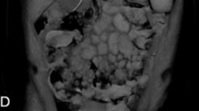

탐폰 사용과 피임 시술 중 어려움을 겪은 여성이 선천적 생식기 이상 진단을 받은 사례가 공개됐다.네덜란드 레이던대 메디컬센터 산부인과 의료진에 따르면, 10대 여성 한 명이 탐폰을 사용했다가 질 안에 걸려 응급실을 내원했다. 의료진은 기구로 제거를 시도했지만 실패했다. 이후 탐폰이 질 내부의 한 조직에 걸려 있다는 사실을 발견했고, 이후 ‘중격 처녀막’ 진단을 받았다. 중격 처녀막은 처녀막 가운데에 얇은 막이 하나 더 있어, 질 입구가 둘로 나뉘어 보이는 선천적 구조다.이후 환자는 몇 년간 무월경을 겪었다. 외부 생식기 구조는 정상이었고, 특별한 건강 이상이 발견되지 않았다. 과도한 운동으로 나타난 증상이라 판단했고, 운동 강도를 줄이자 생리가 자연스럽게 다시 시작됐다.하지만 몇 년 후 자궁내장치를 삽입하던 중 문제가 발견됐다. 자궁내장치가 자궁 한쪽에만 위치한 모습이 확인되면서 쌍각 자궁을 의심했고, 이후 자궁경 검사를 통해 선천적인 자궁 구조 이상이 있다는 사실이 발견됐다. 일반적인 자궁은 하나의 외형으로 이루어져 있지만, 쌍각 자궁은 두 개의 자궁이 합쳐지지 않은 상태를 말한다.의료진은 “처녀막 이상과 자궁 기형은 각각 따로 연구돼 왔지만, 실제로는 함께 나타나는 경우가 꽤 보고되고 있어 그 연관성도 제기되고 있다”며 “다만 그 원인은 아직 정확하게 밝혀지지 않았다”고 말했다. 이어 “처녀막 이상이 진단되면 자궁 등 내부 조직도 추가로 검사할 필요가 있다”고 했다. 자궁 기형을 놓치면 임신이나 시술 때 문제가 발생할 수 있다. 이 사례는 ‘큐레우스’ 저널에 26일 게재됐다.